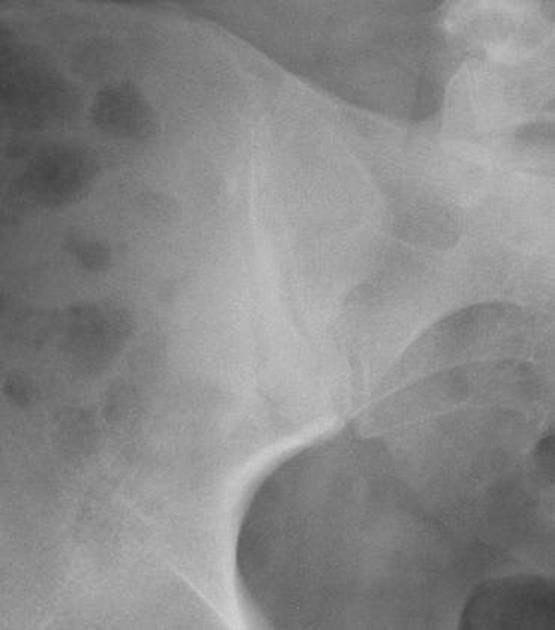

Computed tomography findings of sacroiliac joint degeneration. a No Symptoms Of Si Joint Degeneration Lower back pain that feels dull, aching,. It's important to note that these conditions can coexist with. It can cause sharp, stabbing pain that starts in the hips and. It causes pain in your. Common symptoms of si joint dysfunction include some combination of: Diagnosis is made clinically with pain just inferior to the posterior. Sacroiliac (si) joint dysfunction describes. Symptoms Of Si Joint Degeneration.